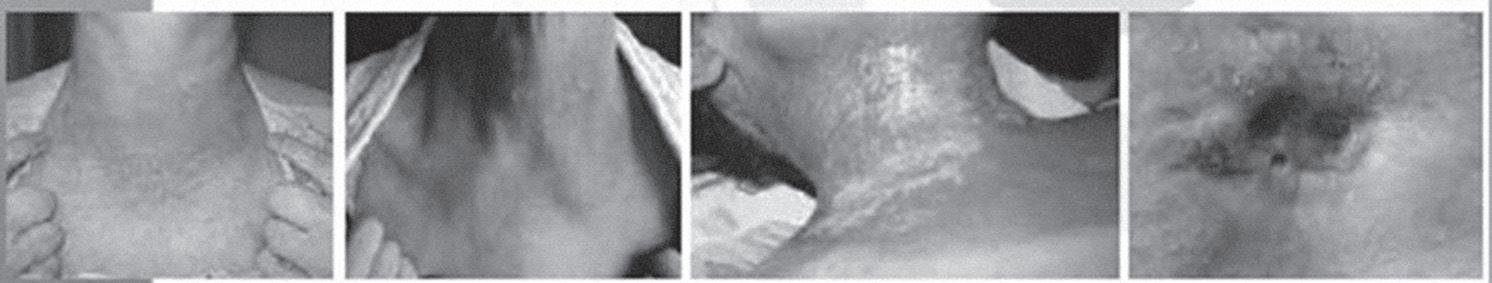

2.6.2 Huidreacties

Ondanks het doel om zo specifiek mogelijk te bestralen zonder omliggend weefsel te beschadigen, zal de patiënt soms te maken krijgen met huidreacties. Die reacties zijn verschillend naargelang de bestralingsregio, dosis, diepte en individuele verschillen van elke patiënt. Zo zal men geen huidreacties ondervinden bij een prostaat- of longbestraling, maar mogelijk wel bij een borstbestraling, rectumbestraling, ORL-tumor, gynaecologische bestraling, huidtumoren en oncologische ulcera.

Voor de radiotherapie start, wordt er een inschatting gemaakt van de huidreactie en speelt men daarop in. De patiënt krijgt preventief advies en wordt gedurende de bestralingsreeks opgevolgd. Als het preventief advies onvoldoende is, zal hier een ander wondzorgadvies voor worden uitgeschreven. Het wordt besproken met de patiënt en eventueel ook doorgespeeld naar de thuisverpleegkundige. De reacties worden op die manier onder controle gehouden zodat infecties vermeden kunnen worden.

Er kan binnen oncologische wondzorg een onderverdeling worden gemaakt tussen een oncologisch ulcus en een oncologische wonde. Beide hebben een classificatiemodel waarbinnen de huidreacties worden onderverdeeld. Een oncologisch ulcus ontstaat doordat er een doorbraak is van maligne cellen door de huid heen. Doordat het om een tumorale reactie gaat, zal men hierbij minder naar wondheling streven, maar naar maximaal comfort en symptoombehandeling. Een oncologische wonde is een wonde die ontstaan is door de tumorbehandeling zelf (zie tabel 1). Een aantal weken na radiotherapie verdwijnen deze huidreacties met een goede wondzorg. Er zijn een aantal aandachtspunten waarop moet worden gelet om de oncologische zorg voor de patiënt zo aangenaam mogelijk te houden. Het belangrijkste doel is streven naar een zo goed mogelijke levenskwaliteit. Daarom opteert men voor een zo eenvoudig en comfortabel mogelijke wondzorg. De wondbehandeling gebeurt volgens het TIME-management (tissue, infection/ inflammation, moisture, epithelialisation).

De patiënt kan tot ongeveer tien dagen na de uitwendige radiotherapie nog extra huidlast ervaren. Na die periode zal de huid zich zo goed mogelijk volledig herstellen. Toch kan er een bruine of donkere verkleuring van de huid zichtbaar blijven.

Na een inwendige bestraling kunnen nog tot ongeveer drie weken na de behandeling huidreacties plaatsvinden, voornamelijk bij inwendige bestraling van huidtumoren. Nadien zal de huid zich ook hier opnieuw gaan herstellen.

2.6.5.2 Bestraling van de halsregio

Acute bijwerkingen

De ernst van de bijwerkingen is sterk afhankelijk van de tumorplaats, de grootte van het bestralingsveld en het fractionatieschema. De meeste klachten verdwijnen ook na de behandeling. Vermoeidheid komt hier ook voor, vaak in combinatie met de andere bijwerkingen zoals bv. gewichtsafname, huidirritatie … De huidtoxiciteit kunnen we terug weergeven aan de hand van tabel 2 (cf. RTOGscoringsysteem).

Huidotoxiciteit kan vermeden worden door rekening te houden met deze tips: - Een vochtinbrengende zalf twee tot drie keer per dag aanbrengen vanaf de start van de RT.

Hierdoor krijgt men reductie van graad III-toxiciteit. - Zonexpositie moet zoveel mogelijk vermeden worden. - Te strakke of synthetische kledij of wrijving met schurende kledij kunnen ook het best vermeden worden. - Qua hygiëne gelden ook hier de bovenbeschreven maatregelen zoals het gebruik van milde zepen, het droogdeppen en droog houden van de huid. Er wordt tevens aangeraden om geen aftershave, deodorant met alcohol of parfum in de bestraalde regio te gebruiken. Elektrisch scheren heeft de voorkeur voor de heren. Tijdens de bestralingsperiode wordt ten stelligste afgeraden om te gaan zwemmen vanwege het uitdrogende effect van de chloor. Kleefpleisters mogen niet aangebracht worden op de bestraalde regio.